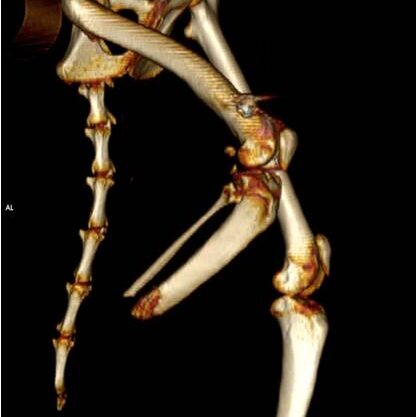

Η διαδικασία ξεκινά με μία αξονική τομογραφία στο Ιατρικό μας κέντρο στην Λευκάδα ή σε κάποιο συνεργαζόμενο με τον κτηνίατρο σας ιατρικό κέντρο. Μέσω αυτής λαμβάνουμε τα απαραίτητα CΤ-images όπου γίνεται ανάλυση  ψηφιακών δεδομένων με χρήση εξειδικευμένου ιατρικού λογισμικού Osirix-FDA.

Το επόμενο στάδιο είναι αυτό της προ-εγχειρητικής μελέτης-διάγνωσης, με σύγχρονες μεθόδους και εξοπλισμό όπως:

Με χρήση εξειδικευμένου μηχανολογικού λογισμικού CAD/CAM/CAE αναπτύσσουμε σε 3D ψηφιακή μορφή:

• την ανατομική περιοχή του οστού σε μορφή 3D όπου θα εφαρμοστεί το εμφύτευμα.

• το εξατομικευμένο εμφύτευμα τύπου ΙΤΑΡ.

• προσομοίωση της εφαρμογής.

• προσομοίωση υπολογιστικής καταπόνησης (κάμψη, θλίψη και εφελκυσμό).